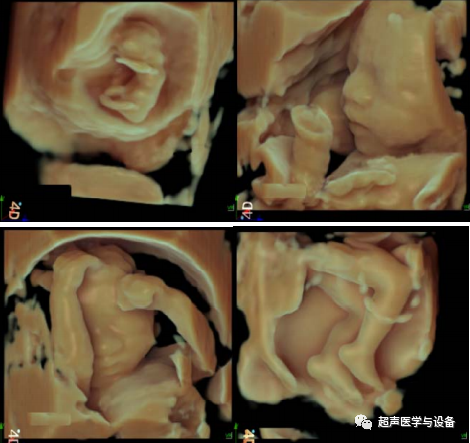

智真光影4D

妇产方面,智真光影4D技术突破更大的三维图像显示区,高效的预备状态裁剪线,通过对光源的控制,让

胎儿更形象生动,栩栩如生。